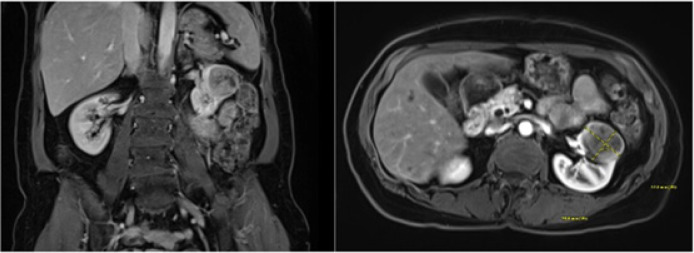

Adenoid cystic carcinoma (ACC) is a rare tumor, accounting for 1% of all head and neck cancers, with an aggressive nature characterized by local recurrence, delayed metastasis, and survival of less than 50% at 10 years. This is a case of biopsy-proven ACC to the kidney, 1 of 29 known occurrences, managed by metastasectomy by robotic-assisted nephrectomy, with plans for resection of lung metastasis. Thirteen years after diagnosis of sinonasal ACC treated with resection, the patient presented with shortness of breath. This prompted a CT scan of the chest, which led to the incidental finding of left renal mass and pulmonary lesion. Literature suggests improved disease-specific survival in locoregional recurrence treated with surgery versus radiation; in patients with metastasis to the lung, metastasectomy offers greater survival benefit than supportive therapy. But, this is not significantly better than chemotherapy or radiation alone. While the optimal therapeutic approach remains to be identified in distant metastatic ACC, metastasectomy remains a viable option for patients who have potentially completely resectable metastatic tumors, appropriate performance status, and adequate affected-organ function. Preoperative counseling should include discussion on partial nephrectomy with prioritization of nephron-sparing but potential for increased perioperative risk versus radical nephrectomy to ensure negative margins and expedite timeline to systemic therapy.

Abstract Image